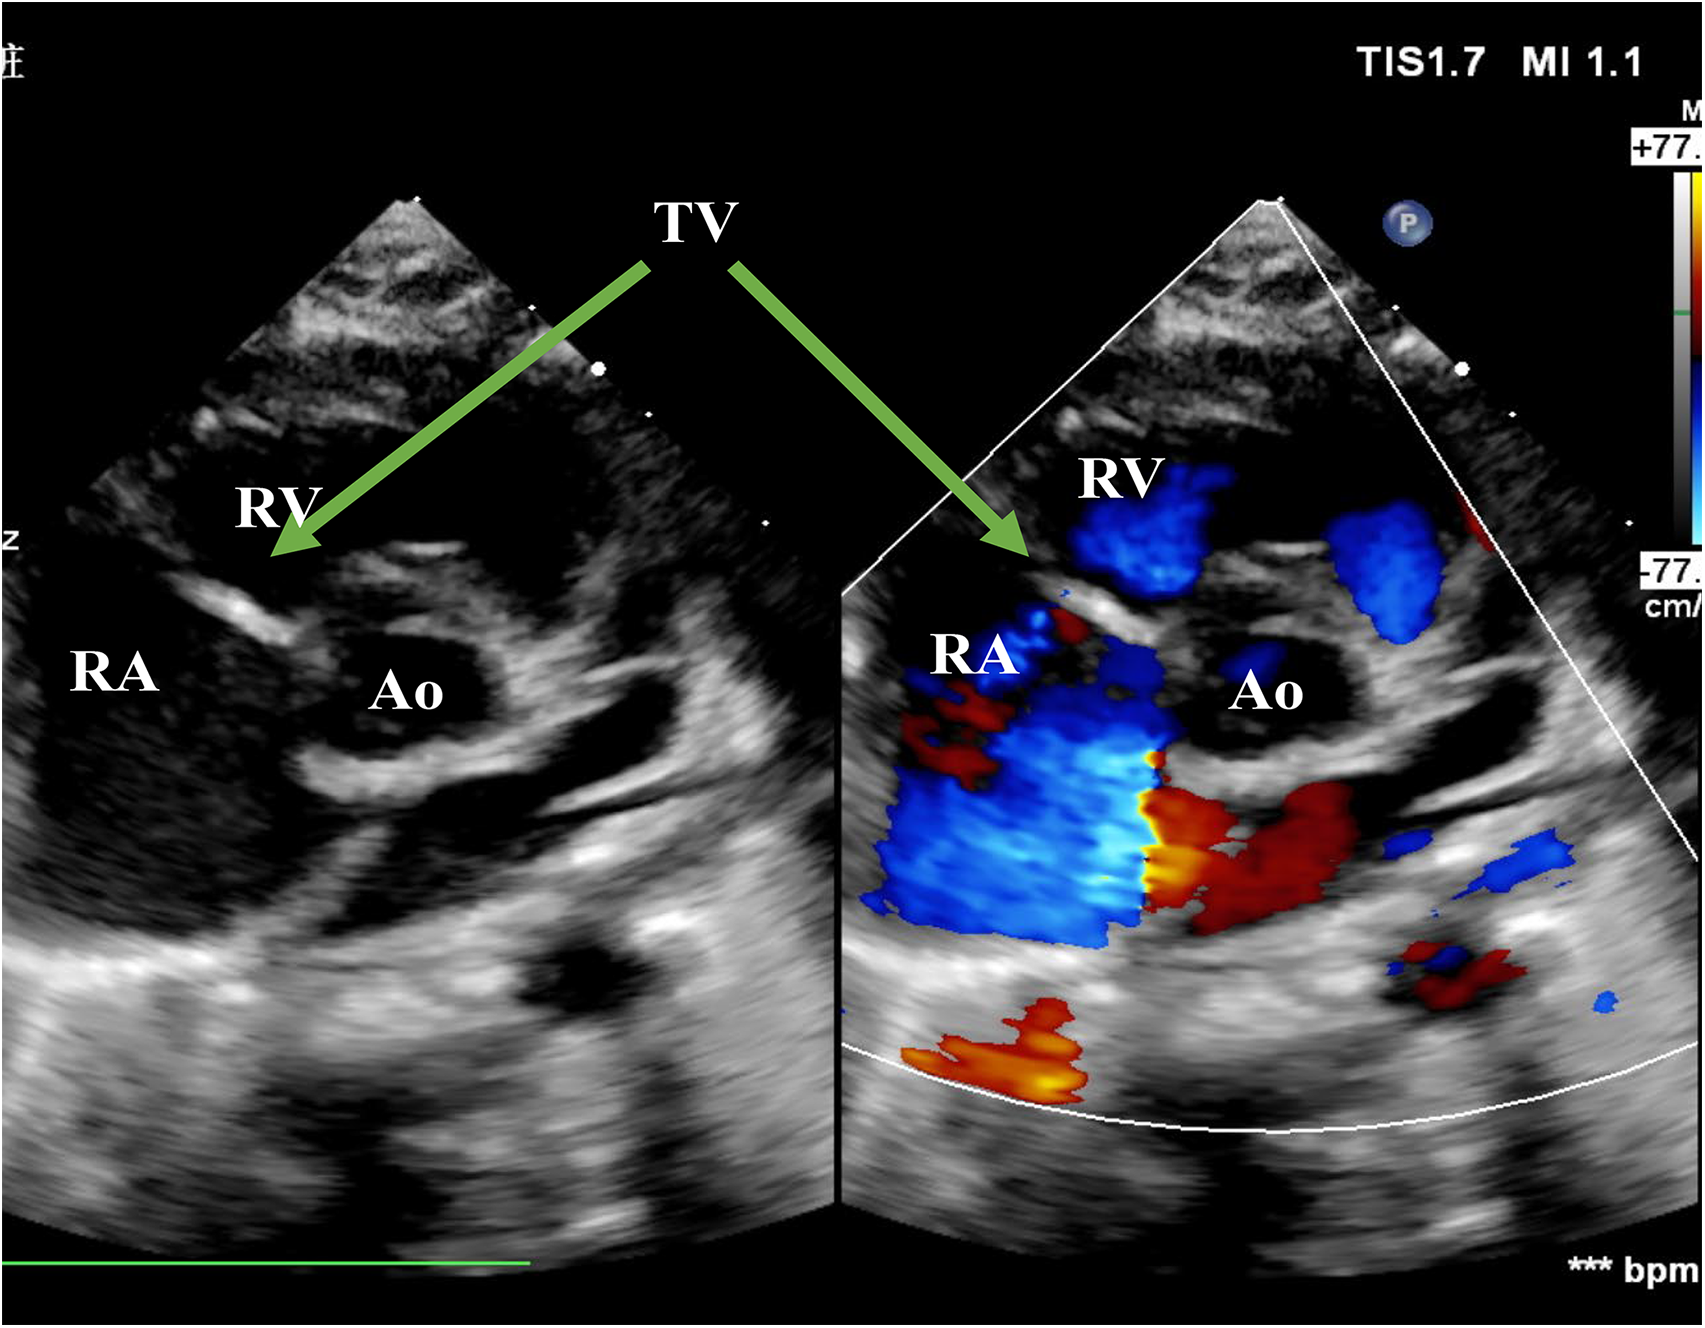

Figure 1

Echo before surgery in the PSAX view. The picture showed severe TR. RA, right atrium; RV, right ventricle; Ao, Aorta; TV, tricuspid valve; PSAX, parasternal short-axis view; TR, tricuspid regurgitation.